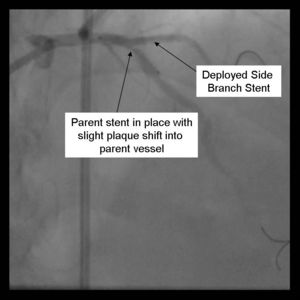

7) The side branch stent is deployed.

8) Angiography should now be performed to ensure adequate side branch coverage and stent deployment. Distal edge dissections or disease should be addressed before parent stent deployment. Once complete, the side branch wire is removed.